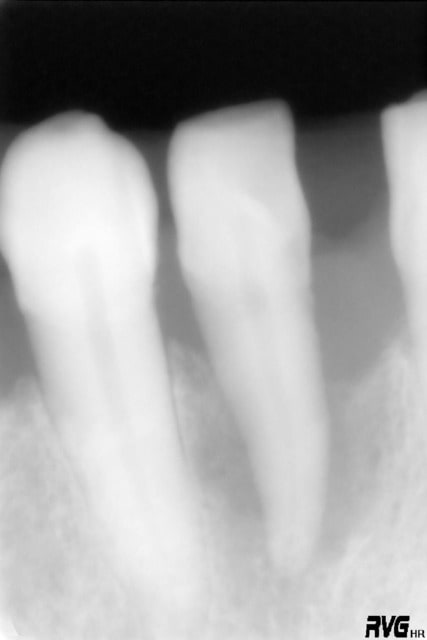

tiens je mets un second cas en mligne avant après et tu me diras ce qyue représente la petite image residuelle en mésial ....canal latéral ?

voici donc ce second cas ....

Oui ça ressemble à un canal latéral non obturé, d'autant que le TR parait étrangement rectiligne, même pour une incisive inf.

La cavité d'accès montre qu'une minéralisation rendait le traitement difficile.

Donc oui, un canal oublié.

Mais je suis tombé dans un piège....non?

c'est pas moi qui est fait l'endo ......d'ac avec toi steph ou ....une petite partie de la table vest a disparu ....par contre le parodonte s'est reformé au dessus